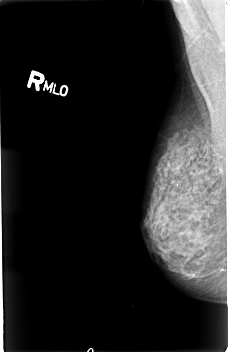

B_3019_1.RIGHT_MLO

RIGHT_MLO LINES 4568 PIXELS_PER_LINE 2960 BITS_PER_PIXEL 12 RESOLUTION 50 NON_OVERLAY